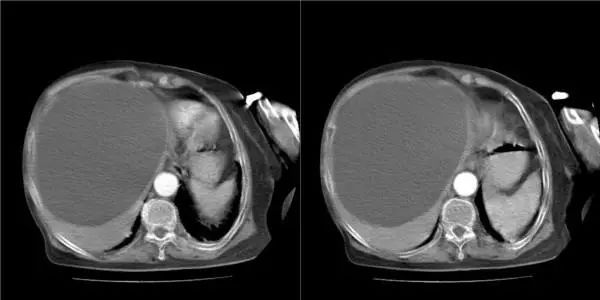

最后刘奶奶通过微创手术,成功摘除囊肿。现刘奶奶术后恢复良好,已康复出院。